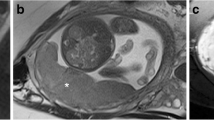

64 patients (n=41 with PAS and n= 23 without PAS) with PP who underwent MRI examination for suspicion of PAS were retrospectively selected. All MRI examinations were acquired on a 1.5 T using T2-weighted (T2w) sequences on axial, sagittal and coronal planes. Ten different manual segmentation methods were performed on sagittal placental T2-weighted images obtaining five sets of 2D regions of interest (ROIs) and five sets of 3D volumes of interest (VOIs) from each patient. In detail, ROIs and VOIs were positioned on the following areas: placental tissue, retroplacental myometrium, cervix, placenta with underneath myometrium, placenta with underneath myometrium and cervix. For feature stability testing, the same process was repeated on 30 randomly selected placental MRI examinations by two additional radiologists, working independently and blinded to the original segmentation. Radiomic features were extracted from all available ROIs and VOIs. 100 iterations of 5-fold cross-validation with nested feature selection, based on recursive feature elimination, were subsequently run on each ROI/VOI to identify the best-performing method to classify instances correctly.

Among the segmentation methods, the best performance in predicting PAS was obtained by the VOIs covering the retroplacental myometrium (Mean validation score: 0.761, standard deviation: 0.116).

Our preliminary results show that the VOI including the retroplacental myometrium using T2w images seems to be the best method when segmenting images for the development of ML radiomics predictive models to identify PAS in patients with PP.